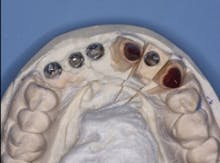

FIG. 3 — Custom “open” tray made from DENTSPLY Triad light-curing material.

FIG. 4 — Custom cast abutments showing compensation for difficult angulation of implant placement.

Using a custom impression tray is the most appropriate method for cases as difficult as the one shown (Fig. 3). Stock trays compromise the practitioner’s ability to make an optimum impression in such situations. I prefer to use light curing tray material. Such material allows the fabrication of any desired tray configuration. An “open” tray design allows the unscrewing of the impression copings before removing the impression from the mouth, optimizing the accuracy of the impression.

FIG. 5 — Incisal view showing proper angulation of abutments.

Fig. 4 shows the parallelism of the three custom cast metal abutments on the patient’s maxillary right anterior area. These three abutments will be splinted together with a three-unit prosthesis. The prosthesis will be cemented with provisional cement (Premier Implant Cement). The cement will be placed only on the most apical third of each abutment when they are cemented to allow subsequent removal of the prosthesis in the event of loose screws or other challenges. Designing abutments to allow space for an optimum esthetic result demands communication between the dentist and lab technician. Fig. 5 demonstrates the homogeneous potential thickness of the subsequent restorations to be placed.